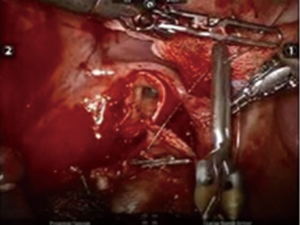

After inserting the ports, the robot was docked. We performed the approach using the three-arm video-assisted thoracic surgery (VATS)-based technique described elsewhere (14). The anterior arm was inserted through a utility incision (Figure 1). The four-arm VATS-based approach was used only in one patient who underwent isolated bronchial resection. The use of V-loc sutures was preferred in the last six cases (Figure 2). As a rule, a prostate bulldog clamp was used to stabilize the first suture (Figure 3). We routinely covered the anastomosis or suture line with pleura, pericardial fatty tissue or rarely with thymus (Figure 4).

There were three primary suture closures, one isolated bronchotomy plus bronchial closure and five bronchial sleeve resections plus anastomosis in our series. Prolene sutures were preferred for bronchial management at first (n=3), but in recent years V-loc sutures (3-0) were used because of technical advantages such as the avoidance of retrograde slippage of the wound’s suture where the tension is greater; in addition, tying a knot is not necessary in case a problem occurs during suturing.